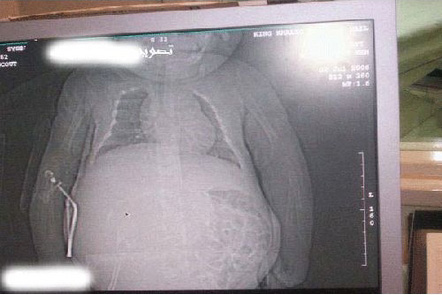

僅か1歳の赤ん坊が妊娠?!

20090430baby1.jpg22年間凍らせていた精子で子供を授かる人も いるかと思えば、性行為もしていないのに「妊娠」してしまった人もいるようです! サウジアラビアで生まれた赤ん坊が、なんと、生まれた時点で「受胎」をしていたのです。昨年末に発覚したこの赤ん坊の一件は世界的に見ても超稀なケース で、衝撃的な写真を目撃したユーザーの多くはあんぐりです。

この子はサウジアラビアで生まれた女の子です。

一見、普通の赤ん坊に見えますが、少しお腹が大きいですよね。レントゲンを見てみると…お腹がやはり大きく膨らんでいます。更に拡大していくと胎児の姿がうっすら見えます。どうやったら赤ん坊が妊娠するなんてことが起こるのでしょうか。20090430baby2.jpgそれは、母親の胎内で受精卵が2つに分化し、一つの胎芽がこ の赤ん坊の子宮に入ってしまったのです。つまり、この子のお腹に写っている命は自分の双子の兄弟なのです! 兄弟を受胎しているのです。医学史上、似たような事例は過去に51回あったそうですが、その確率は500,000人に1人と言われているそうです。中でも最も衝撃的な事例は、インド人男性が36年間気付かずに双子の兄弟を体内で「育成」し続けていたケース。このニュースは私も覚えていました。ピノ子みたいだと思った記憶が・・・医者からは腹部に腫瘍があると言われ、見てみると人間の髪の毛や 顎の骨、性器などが見つかったとのこと。驚きです。

20090430baby3.jpg今回の件で、医師たちはこの女の子を救うためにどのように「流産」させるかを検討しているそうです。妊娠している赤ん坊を救うために胎内の兄弟が犠牲にならなければいけないという可能性もあって難しいです。やっぱりブラックジャックが必要です!産まれながらに妊娠している、しかも、それが自分の双子の兄弟だなんて・・・・・。兄弟の命がどうなってしまうかは定かではありませんが、この女の子の将来に悪影響がないことを祈りましょう。    photo by momlogic